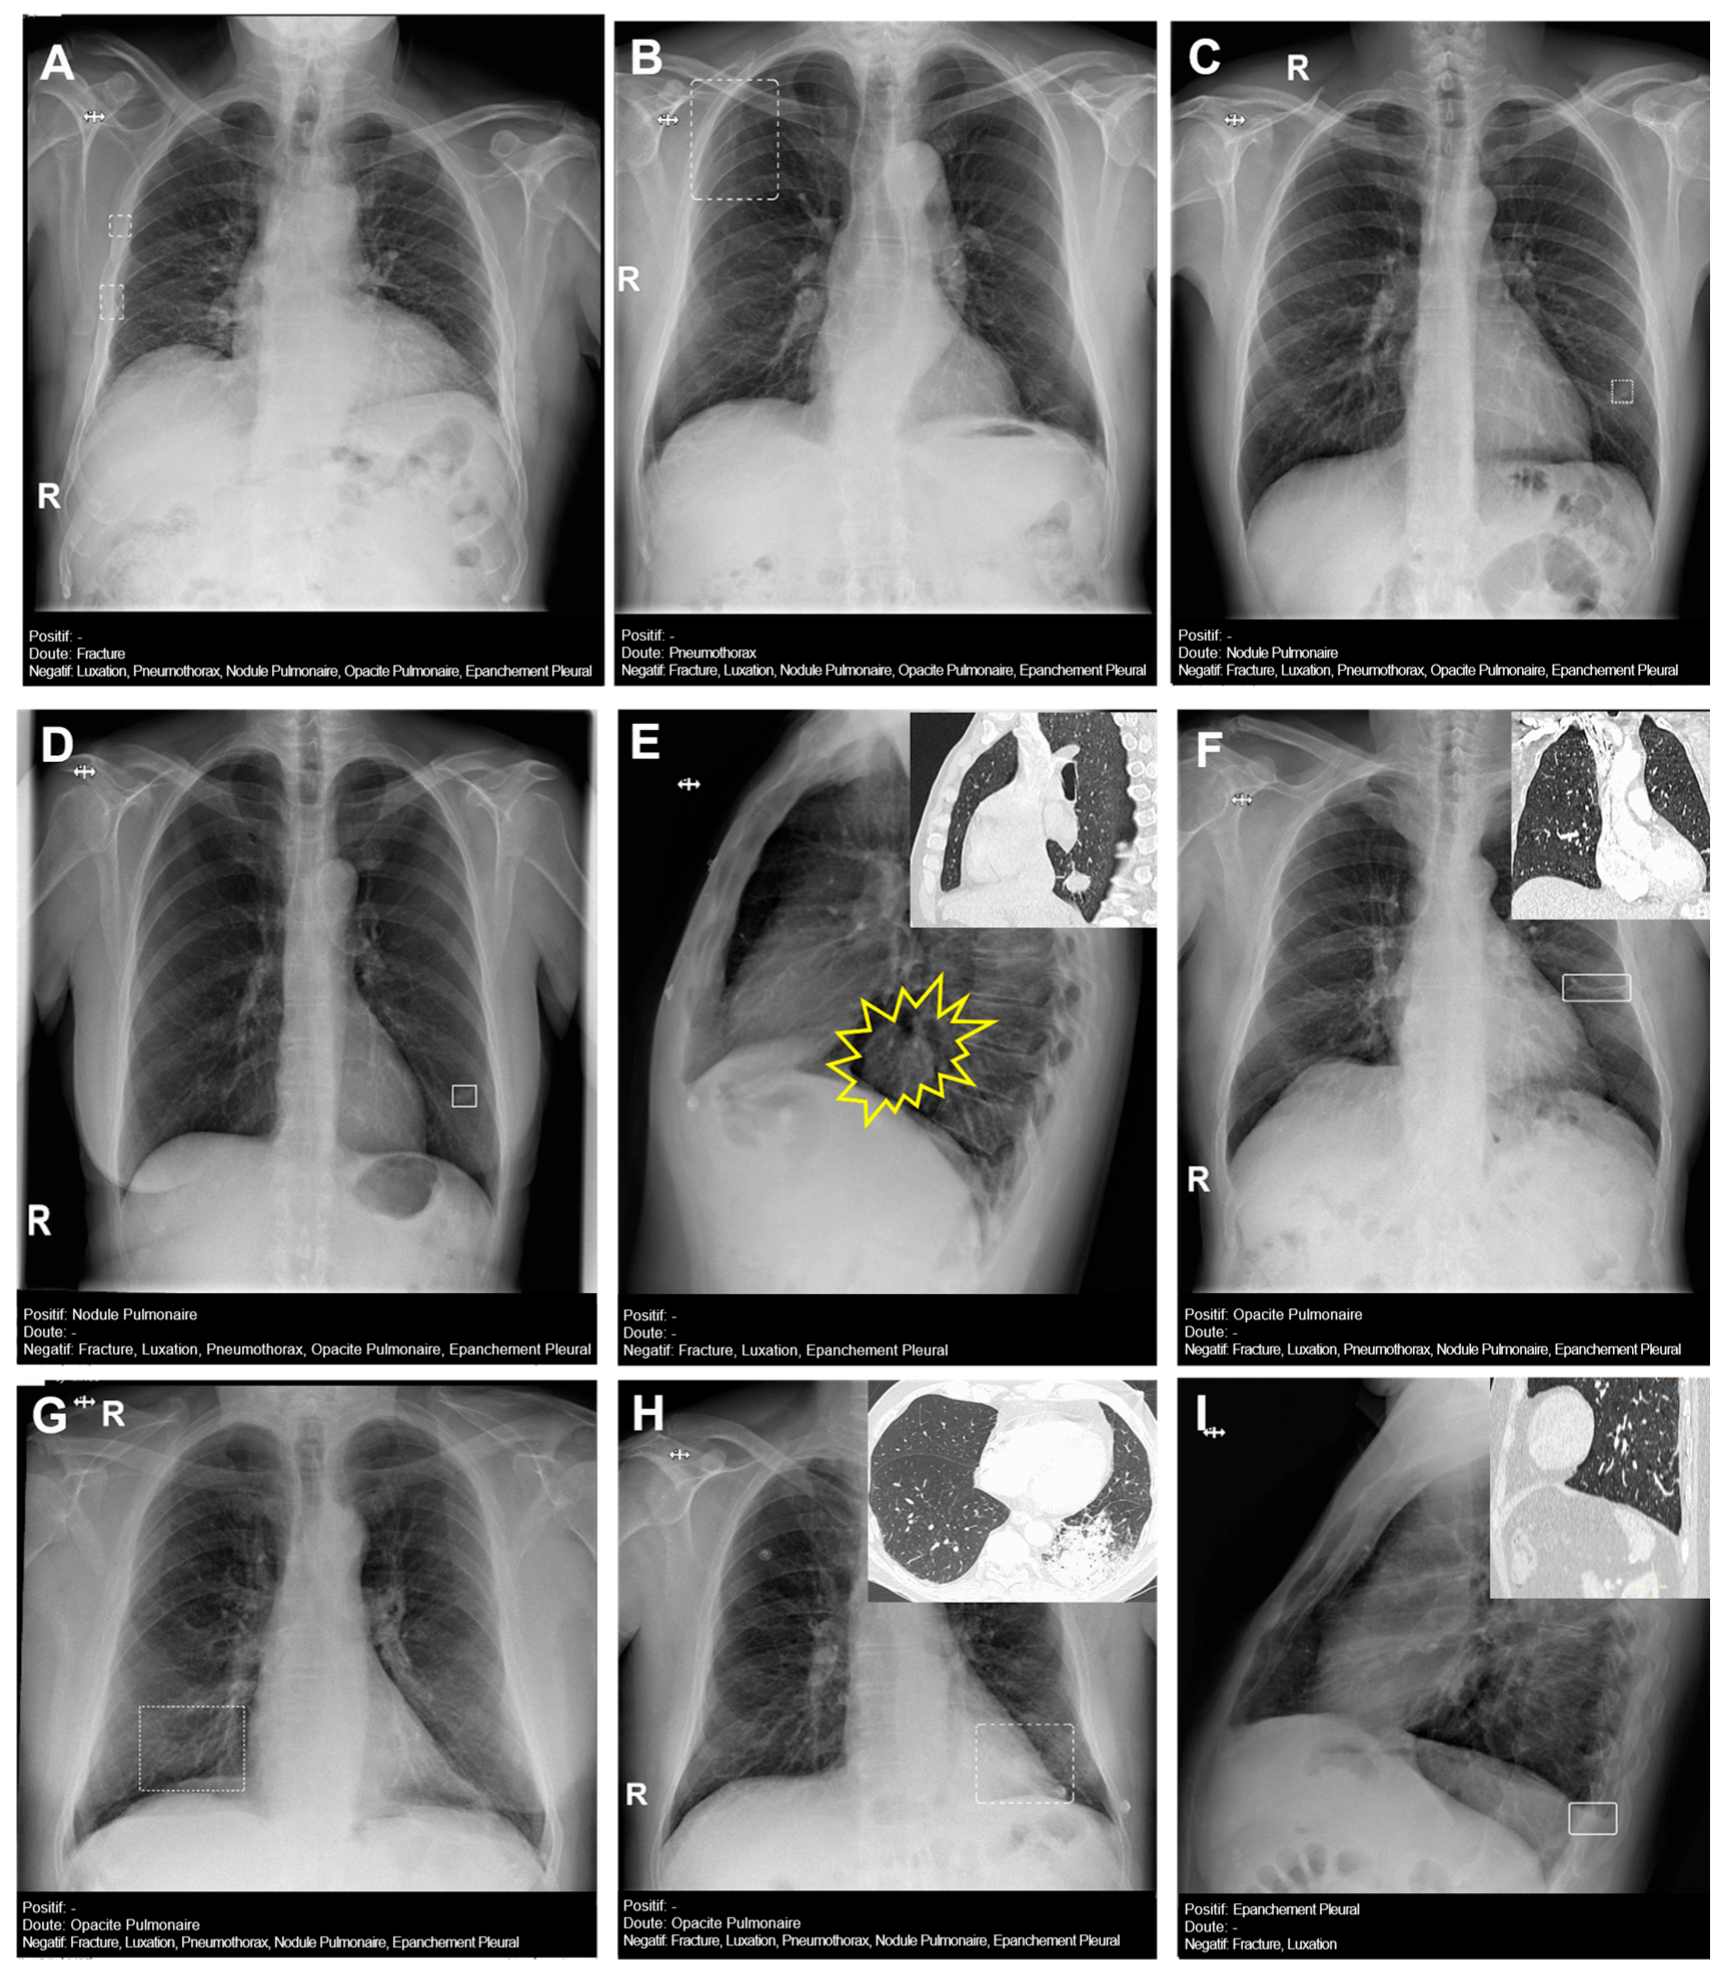

Figure 4 presents several examples of chest radiographs analyzed by the AI.

Figure 4. Chest radiographs with AI analysis (and E,F,H,I with the associated sagittal (E,I), coronal (F), and axial (H) CT images). (A) False doubtful right fractures outlined with discontinuous boxes (they are chronic). (B) False doubtful right pneumothorax outlined with a discontinuous box. (C) False doubtful left lower lobe nodule outlined with a discontinuous box. (D) False positive left lower lobe nodule outlined with a continuous box. (E) False negative left lower lobe nodule; there is a nodule (outlined in yellow). (F) False positive left pulmonary opacity outlined with a continuous box (it is a laminar atelectasis). (G) False doubtful right lower lobe opacity outlined with a discontinuous box (it is normal pulmonary vascularization). (H) True doubtful left lower lobe opacity outlined with a discontinuous box (retrocardiac infection). (I) False positive pleural effusion outlined with a continuous box (it is a subtle non-pathological erasure of the posterior costophrenic angle).